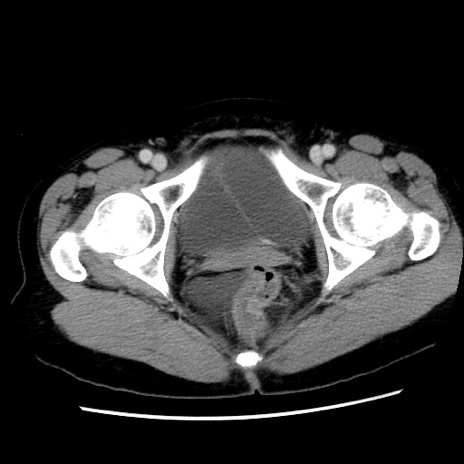

症例10(横断像)

【症例】 50歳代女性

【主訴】 腹痛

【現病歴】前日生レバーを食べた。今朝に排便あり。 昼前に突然発症の腹痛を生じ、当院救急外来を受診した。

【既往歴】 子宮筋腫にてで子宮全摘後

【身体所見】 意識清明、腹部:平坦、軟、下腹部やや左を中心に圧痛・反跳痛あり、筋性防御あり

【データ】WBC 7800、CRP 0.07